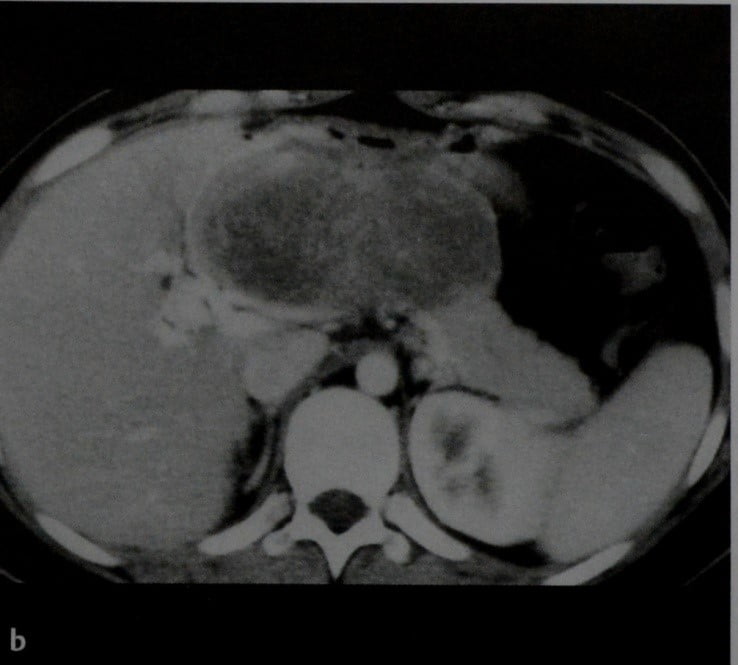

КТ-исследование абсцесса малого таза: Визуализация и диагностика

Раздел: Фотоальбом решений